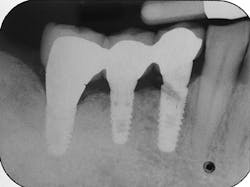

The most critical aspect of any implant system is the interface between the implant fixture and its surrounding bone (figures 1-5). Integration between the fixture and its surrounding bone is the foundation of modern implant dentistry. There is little we can do to modulate bone healing, but we can modify the implant fixture itself.

Figures 1-5: Figures 1 through 4 illustrate, respectively, a seven-year follow-up visit and a three-year follow-up visit of two different implant systems. Implant No. 22 (figure 5) shows peri-implant radiolucency following functional loading, indicating fibroencapsulation and loss of integration into bone, necessitating removal.